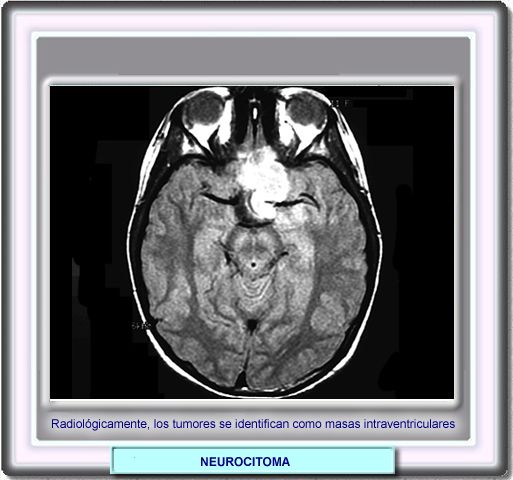

NEUROCITOMA